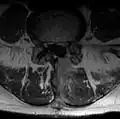

Bei dieser Operation wurde der gesamte Wirbelbogen auf der betroffenen Seite entfernt. Der Spinalkanal ist nicht mehr gut einsehbar, hier ist Blut eingedrungen -

Nukleotomie

Hier das gleiche Bild, zur besseren Übersicht ohne eingebauten Text. Sehr deutlich ist das Narbengewebe zu sehen, das sich neben dem Dornfortsatz bis an den Wirbelbogen bildet